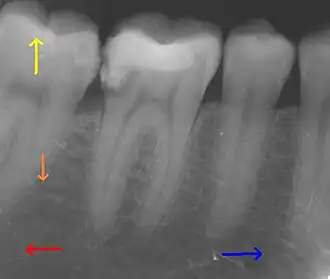

This X-ray film depicts some of the teeth in the lower right quadrant. The arrows point in the following directions: distal ←, mesial →, coronal ↑, apical ↓.